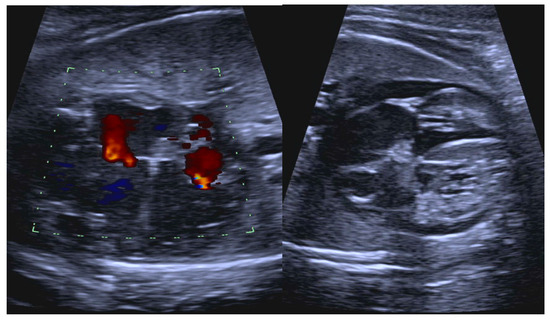

- Atrial flutter (AF) due to a macro-re-entrant pathway within the atrial myocardium and associated with varying degrees of AV block (Figure 2).

- Short VA SVT (Figure 3 and Figure 4) demonstrates a ventricular–atrial (VA) interval that is less than half of the ventricular–ventricular (VV) interval (VA:AV ratio < 1) and a sudden onset and termination of tachycardia; tachycardia usually terminates with a non-conducted atrial contraction. Short VA SVT includes AVRT (also known as orthodromic reciprocating tachycardia, ORT) and atrioventricular nodal reentrant tachycardia (AVNRT). Short VA SVT typically presents after 18 weeks of gestation.